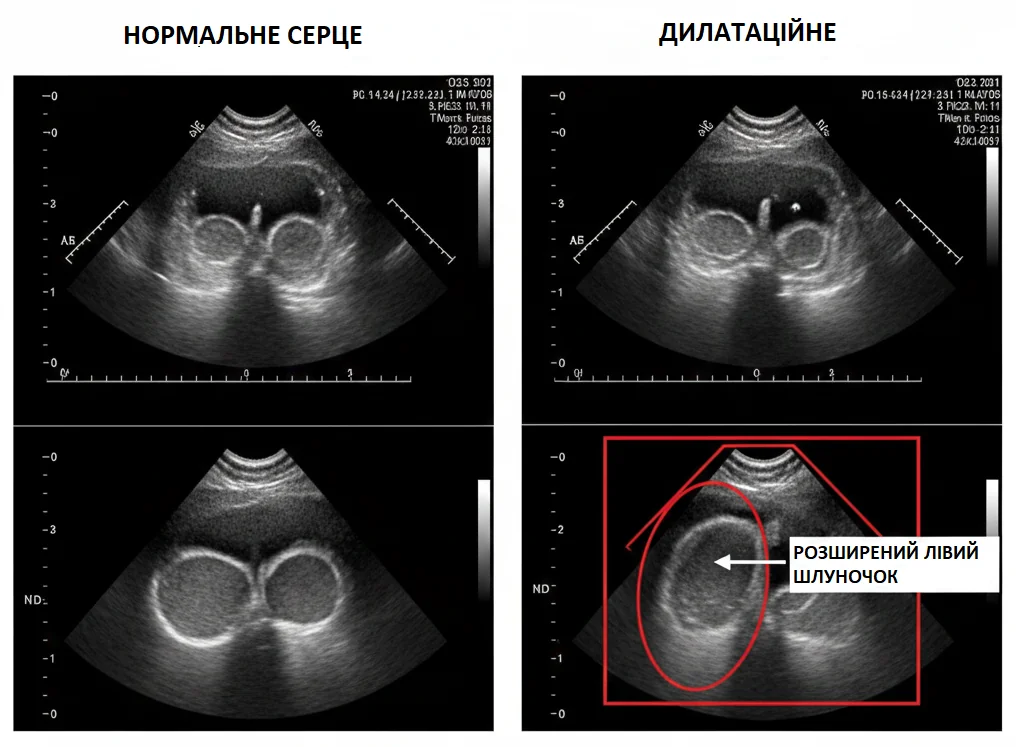

Проблема нутритивної дилатаційної кардіоміопатії стала предметом активних дискусій після публікації звітів fda щодо зв'язку цієї патології з беззерновими дієтами. Йдеться про корми з високим вмістом бобових культур: гороху, нуту та сочевиці, які можуть негативно впливати на метаболізм таурину в організмі собак. В АртВет ми аналізуємо ці ризики з точки зору кардіології: дефіцит специфічних амінокислот або вплив антинутрієнтів веде до поступового зниження скоротливої здатності міокарда та розширення камер серця.

Для пацієнтів, які тривалий час перебувають на раціонах з обмеженим набором інгредієнтів або беззернових сумішах, ми в АртВет рекомендуємо регулярний кардіоскринінг. Ехокардіографія дозволяє виявити ранні ознаки зміни структури серця ще до появи задишки чи непереносимості фізичних навантажень. Наша мета полягає у вчасному виявленні нутритивних дефіцитів та корекції дієти, що в багатьох випадках дозволяє зупинити прогресування хвороби або навіть досягти часткової регресії структурних змін серцевого м'яза.